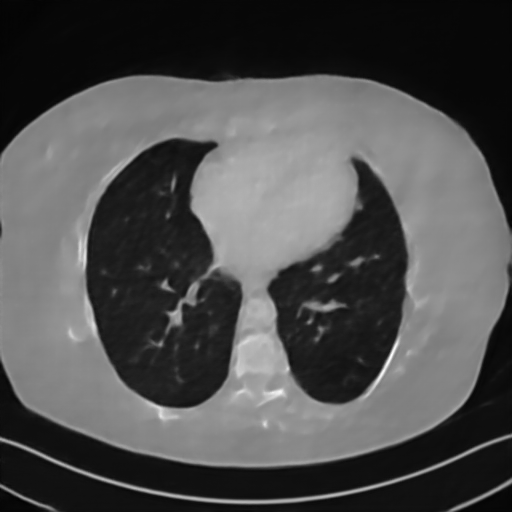

Fig. 4 presents the reconstruction results and residual images obtained by different methods for limited-angle reconstruction. As can be seen, the learning-based methods outperform the direct method and TV model, which exhibit serious artifacts in the missing angle region. Although the denoiser introduced by the FBP-Unet can somehow deal with the noises, the result still presents obvious artifacts. Compared to the SIPID, PD-net and FSR-nets, our LRIP-net1/2 can better preserve the image details and edges with less information left in the residual images. Thus, both the quantitative and qualitative results confirm that the low-to-high double-resolution strategy can improve the reconstruction accuracy for the limited-angle reconstruction problem.

We observe that the low-resolution image prior plays an important role in our method. More specifically, we compare the results of our LRIP-net with respect to different low-resolution priors, which are obtained by down-sampling rate of 1/2, 1/4, and 1/8, respectively. As can be seen in Table III, the best reconstruction results are obtained with the image prior reconstructed by the down-sampling rate of for 150∘, 120∘ and 90∘ limited-angle reconstruction. The visual comparison based on different image priors are also provided in Fig. 5, where obviously less artifacts are left in the reconstruction image by LRIP-net1/8. By comparing the running time, it is easy to see that the smaller the low-resolution image prior, the faster the LRIP-net works.